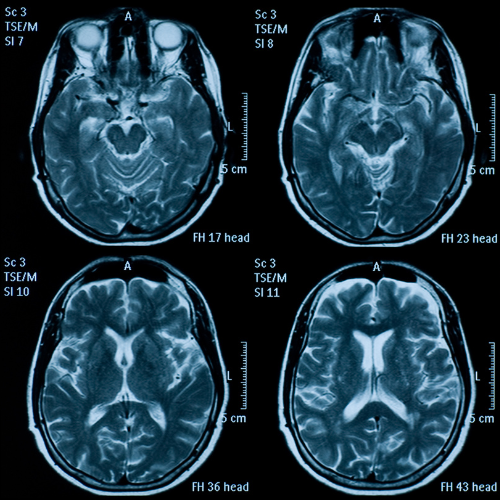

Los sujetos se sometieron a una resonancia magnética craneal, al principio y dos años después del tratamiento. Estos análisis, junto con los análisis del plasma, mostraron que en los sujetos con concentraciones elevadas de ácidos grasos, el tratamiento con vitaminas había ralentizado la tasa de crecimiento de la atrofia en un 40,0% en comparación con el placebo.